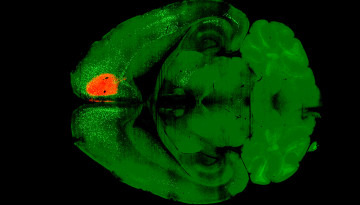

An international collaboration led by Cornell researchers used a combination of psilocybin and the rabies virus to map how – and where – the psychedelic compound rewires the connections in the brain.